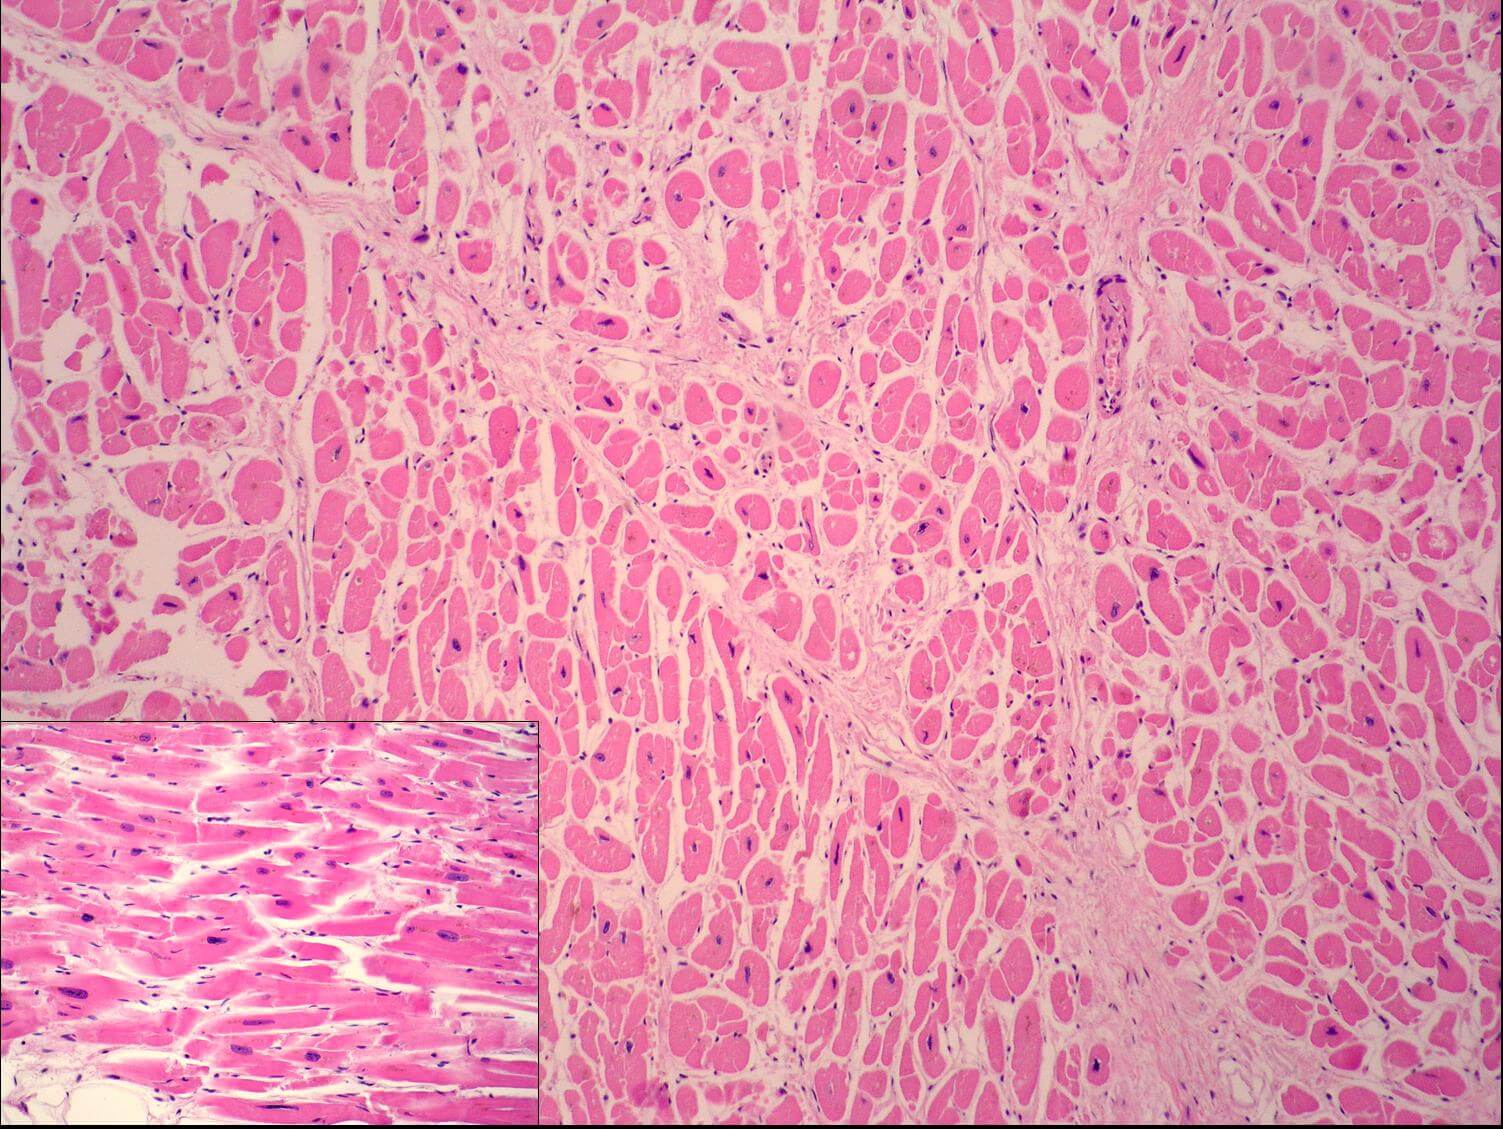

В процессе занятий в тренажёрном зале человек тренирует мышцы скелета, состоящие из миофибрилл и саркомеров. Вместе они образуют мышечное волокно. Человек имеет 650 скелетных мышц. Они сжимаются, когда поступает команда от моторных нейронов. Через нервные импульсы моторные нейроны «сообщают» мышцам, что надо сократиться. Чем лучше налажена эта связь, тем активнее идет сокращение мышечных волокон.

Что такое гипертрофия мышечного волокна?

В результате регулярных физических нагрузок наблюдается постепенное увеличение мышечной массы. Это и называют мышечной гипертрофией. Увеличение мышц в объемах требует особых условий и происходит, если человек регулярно увеличивает нагрузку, переступая тот барьер, к которому организм успел уже адаптироваться.

Есть разные виды гипертрофии:

| Вид | Описание |

| Миофибриллярная гипертрофия | Это когда мышечная ткань уплотняется за счет плотности миофибрилл. Появляется жесткость, сила в руках и ногах, выносливость. Но сам объем мышечной ткани остается прежним. |

| Саркоплазматическая гипертрофия | Это когда увеличиваются сами клетки в поперечном сечении, но их сила остается прежней, не растет. Зато повышается выносливость. За счет этого появляется возможность заниматься дольше, не уставая. |